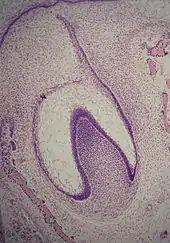

Le début de l'agencement des cellules dans le bourgeon dentaire se produit au stade de la cupule. Dans le mésenchyme, tissu conjonctif, un petit groupe de cellules cesse de sécréter le substrat extracellulaire qui les entoure, ce qui va se traduire par un rapprochement des cellules entre elles et former la papille dentaire. À ce stade, le bourgeon dentaire se développe autour de cet agrégat, prenant la forme d'une cupule et devient l'organe de l'émail. Des cellules du mésenchyme vont s'agglomérer autour de l'organe de l'émail et de la papille dentaire pour former le follicule dentaire. La papille dentaire va alors produire la dentine et la pulpe, l'organe de l'émail va produire de l'émail et le follicule dentaire produire le parodonte, les structures de soutien de la dent[1].

Stade de la cloche

Le stade de la cloche est celui des différenciations histologiques et morphologiques. L'organe de l'émail y prend une forme de cloche et la majorité de ses cellules forment le réticulum étoilé, nom dû à leur forme en étoile[1]. Les cellules de la périphérie de l'organe de l'émail se répartissent en trois couches importantes : les cellules cubiques situées à la périphérie de l'organe de l'émail forment l'épithélium adamantin externe ou latéral[2] ; Les cellules cylindriques de l'organe de l'émail situées du côté de la papille dentaire forment l'épithélium adamantin interne ou médial et les cellules entre l'épithélium adamantin interne et le réticulum étoilé forment une couche connue sous le nom de stratum intermedium. La zone où les épithéliums externe et interne de l'organe de l'émail se rejoignent est appelée l'anse cervicale[7].